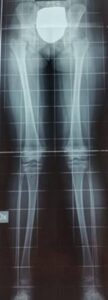

E’ fondamentale in preparazione ad un’eventuale chirurgia, eseguire una radiografia in maniera corretta. Questo consente di calcolare gli assi meccanici e quantificare a pieno la deformità. Non è infrequente infatti una discrepanza tra esame clinico e esame radiografico: può capitare che pazienti che mostrano un valgismo significativo clinicamente, abbiano poi in realtà una deviazione dell’asse modesta, che non necessita di un intervento chirurgico.

Per essere eseguita correttamente ed evitare errori di misurazione, la radiografia degli arti inferiori effettuata in piedi. Devono essere visualizzati femore e tibia sulla stessa immagine in modo da poter effettuare il calcolo degli assi, devono essere visualizzati il bacino e l’ala iliaca per verificarne i nuclei di crescita (Risser e cartilagine triradiata).